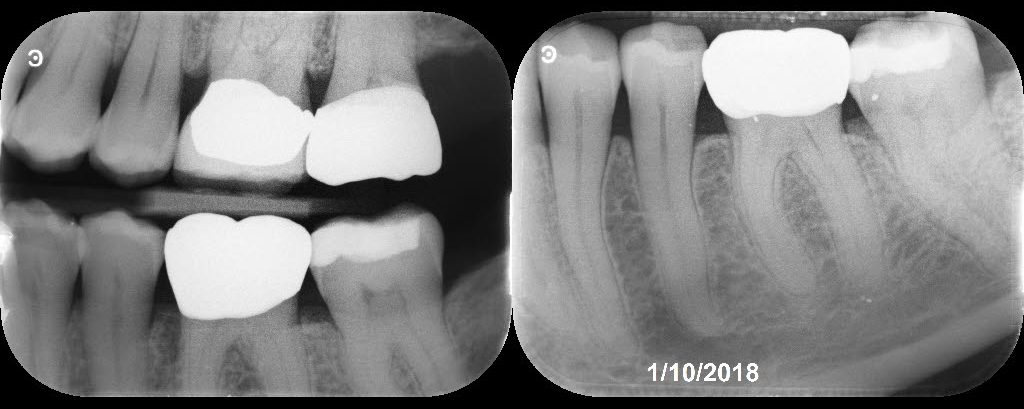

Restoring with Amalgam. 72yom. The patient had avoided the dentist due to dental anxiety. Tooth #3(16) SIP and #2(17) responded normally to all clinical tests. I recommended attempting to save both molars but he hesitantly agreed to start with tooth #3. Image Guided Treatment using CBCT aided in confirming the presence and location of MB2. […]